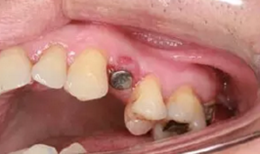

種植手術(shù)完成2周后進行拆線??梢钥闯鲕浗M織愈合良好。

圖8 拆線時的口內(nèi)照片